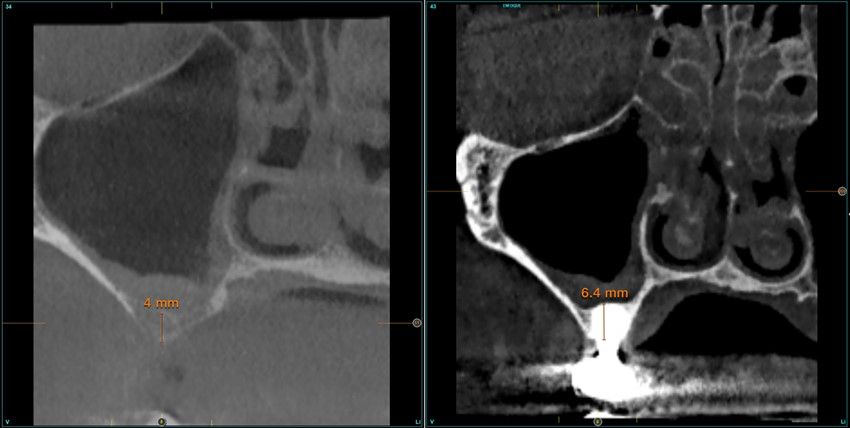

Resultados. Fueron reclutados 13 pacientes en los que se insertaron 30 implantes. Una vez insertados y cargados los implantes, la altura media final fue de 9,68 mm (+/- 2,66), lo que supone una ganancia promedio de 5 mm. A los 10 años, se observó una disminución media de la altura ósea ganada en los implantes en conjunto de 0, 29 mm (+/- 0,77). La media de la pérdida ósea mesial fue de 0,73 mm (+/- 0,75 mm) y la media de la pérdida ósea distal fue de 0,98 mm (+/- 1,2 mm). La supervivencia fue del 100%.

Results.Thirteen patients were recruited and 30 implants were inserted. Once the implants were inserted and loaded, the mean final height was 9.68 mm (+/- 2.66), which represents an average gain of 5 mm. At 10 years, there was a mean decrease in the overall bone height gain of the implants of 0.29 mm (+/- 0.77). The mean mesial bone loss was 0.73 mm (+/- 0.75 mm) and the mean distal bone loss was 0.98 mm (+/- 1.2 mm). Survival was 100%.

Los senos tratados con la técnica de elevación transcrestal sin material de relleno muestran un incremento de entre 2,5 mm12,13 hasta 4.4 mm14,15 en la altura ósea lograda sobre el ápice y una supervivencia de los implantes que se sitúa entre un 94 y un 100%16-17. En este trabajo se presenta un estudio retrospectivo donde se ha evaluado la inserción de implantes extracortos (5,5 y 6,5 mm) en zonas posteriores maxilares mediante la técnica de elevación de seno transcrestal con la fresa de ataque frontal sin la utilización de material de injerto, con un tiempo de seguimiento de 10 años para poder objetivar el comportamiento de los implantes a largo plazo y de la técnica empleada.